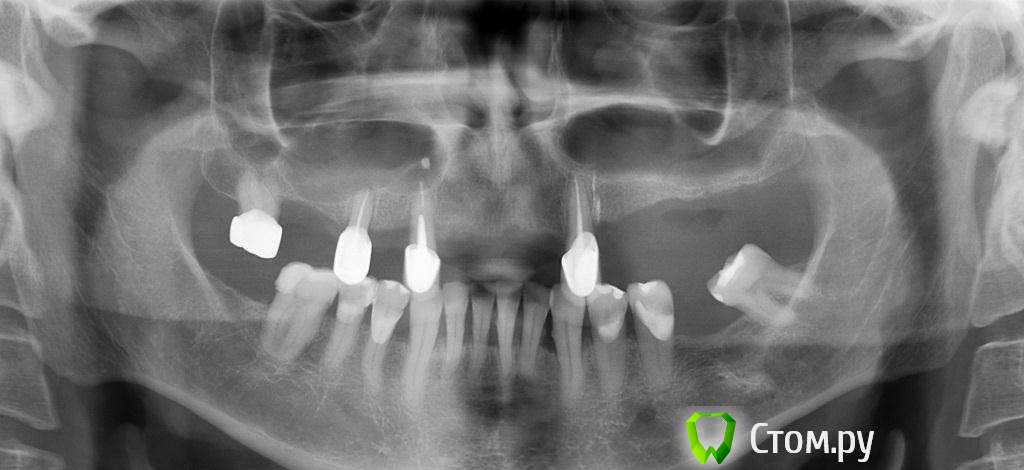

zzkz Опубликовано 2 сентября, 2014 Поделиться Опубликовано 2 сентября, 2014 (изменено) Запланировал сделать все сразу-фронт, слева и справа.На правую сторону не пошел, кончились стерильные винты 1. Синус от 2.4 до 2.7, НКР в области 242. НКР от 1.2 до 2.2 В пазуху ушло 2 мп3, 2 биоса При установке ламины винт прорезался, заштопал Еще раз прорезался винт и еще раз.. Помоему в пазуху переборщил с материалом? Фото кровавые, корявые, не знаю как вы делаете все чистенько. Спасибо болшое, что на форум выкладываете как можно бороться с непредвиденными ситуациями, в частности заплатка на ламину. Что бы делал если не показывали Жду критики.Как бы вы поступили при схожем случае? Изменено 2 сентября, 2014 пользователем zzkz 8 Ссылка на комментарий